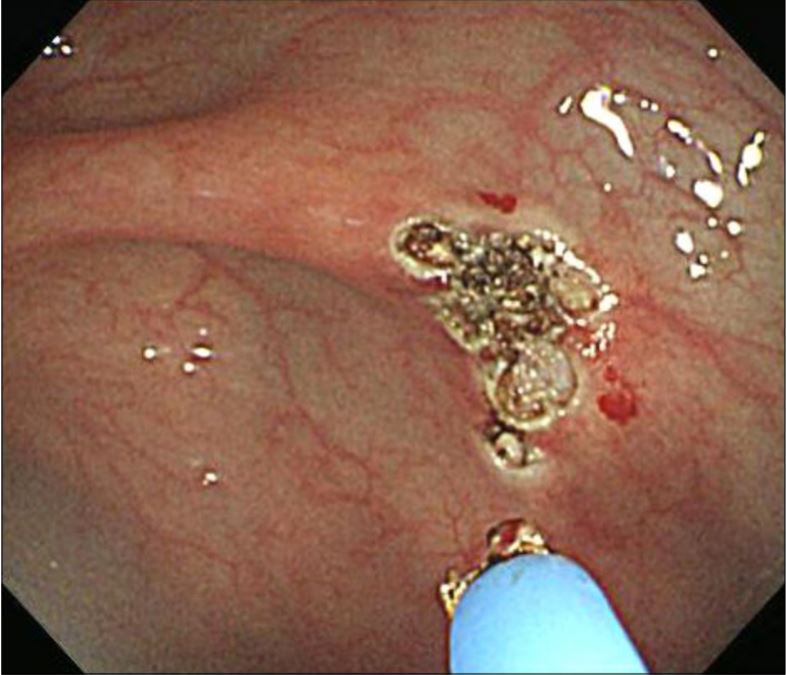

🔘video capsule endoscopy (pic1⬇️ = small bowel AVM)